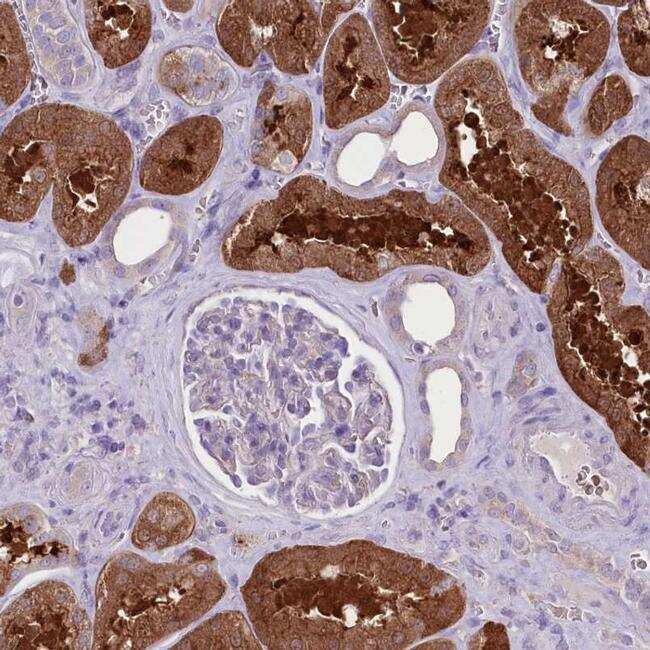

- Immunohistochemical analysis of PRSS53 in human kidney using PRSS53 Polyclonal Antibody (Product # PA5-57092) shows secreted/cytoplasmic positivity in proximal tubules.